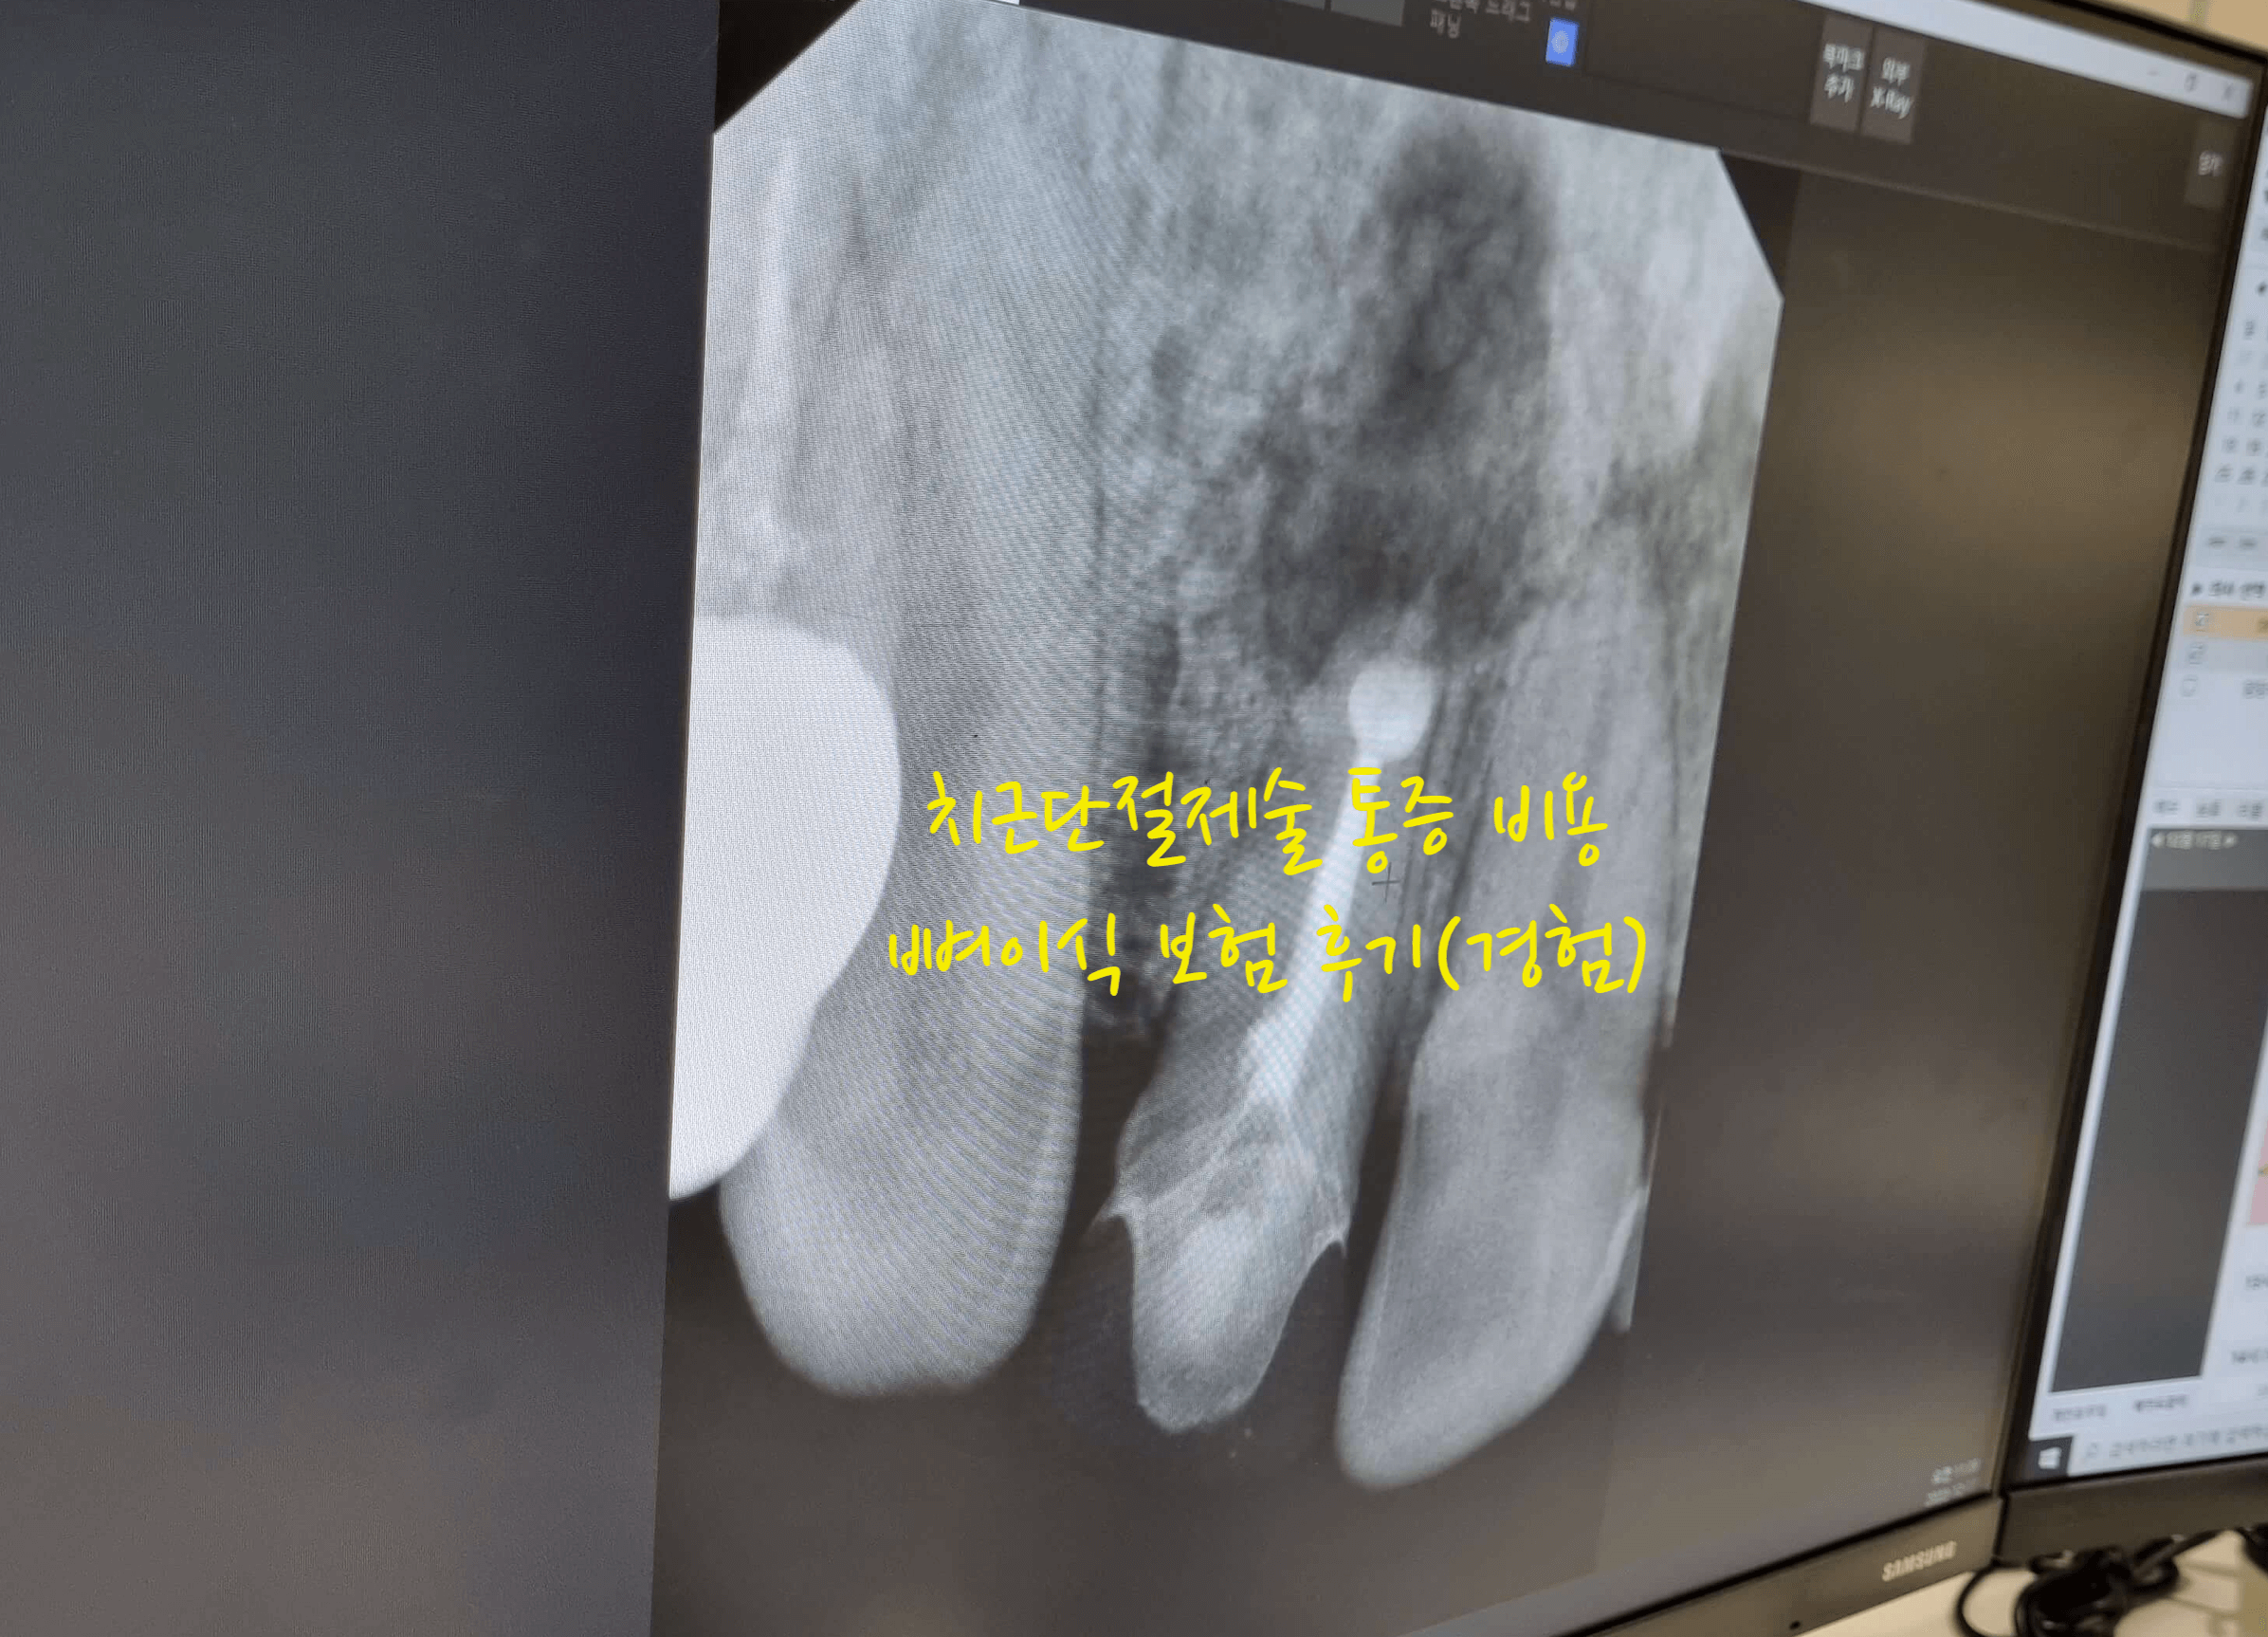

그러다가 시간이 흐르니 심한 통증을 느끼게 되고 또 하루 이틀지나면 괜찮아서 그냥 약먹고 지냈는데, 치과를 바꾼후 엑스레이를 찍었는데, 치과 의사선생님이 이거 이대로 방치하면 안되다고 염증이 뼈를 녹이고 있어서 치아를 뽑아 염증을 제거하던지 치근단 절제술을 해서 염증을 빼던지 해야 한다고 했습니다.

그렇게 오랜시간 치아뿌리에 염증을 방치 했더니 염증이 주변의 뼈를 녹여서 구멍이 나있는 수준이였습니다. 이렇게 염증을 계속 방치하는 경우 뼈를 녹이는 범위가 넓어져 전체적인 치아뼈대에 문제가 발생할수도 있기 때문에 염증이 있다면 바로 치료 및 조치를 받아야 합니다.

임플란트할때도 뼈이식을 했는데, 치근단절제술은 특히 앞니 잇몸쪽을 절개해서 뼈를 이식하고 염증을 제거해석 그런지 몰라도 다시는 하고 싶지 않은 좋지 않은 통증을 느꼈습니다. 위 사진을 보시면 제법 아파 보이는데, 그렇게 못참을 만큼 아픈건 아니지만 임플란트 해넣는것 보다는 통증이 아프다고 말하고 싶네요.